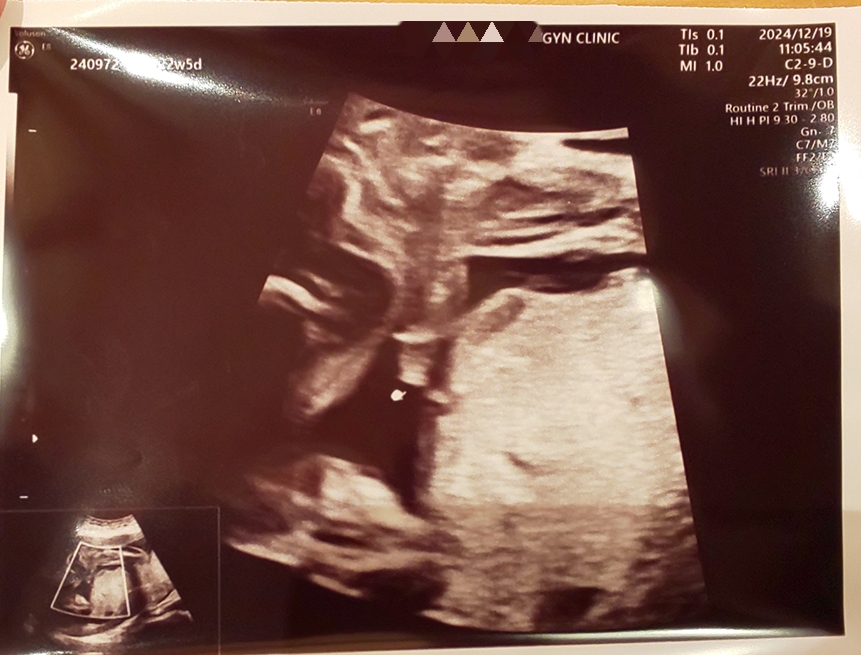

12/19 22w5d

4Dエコーではこちゃの動きが激しく腕をシタバタさせていたために今回も顔見れず…。先生が念のため再度性別確認してくれて、2度目のお股のエコー写真を貰いました笑(指さしカーソルあるところがおちん)私の声によく反応しているらしく、先生から「この子は胎動激しいと思う」とお墨付きをもらいました。